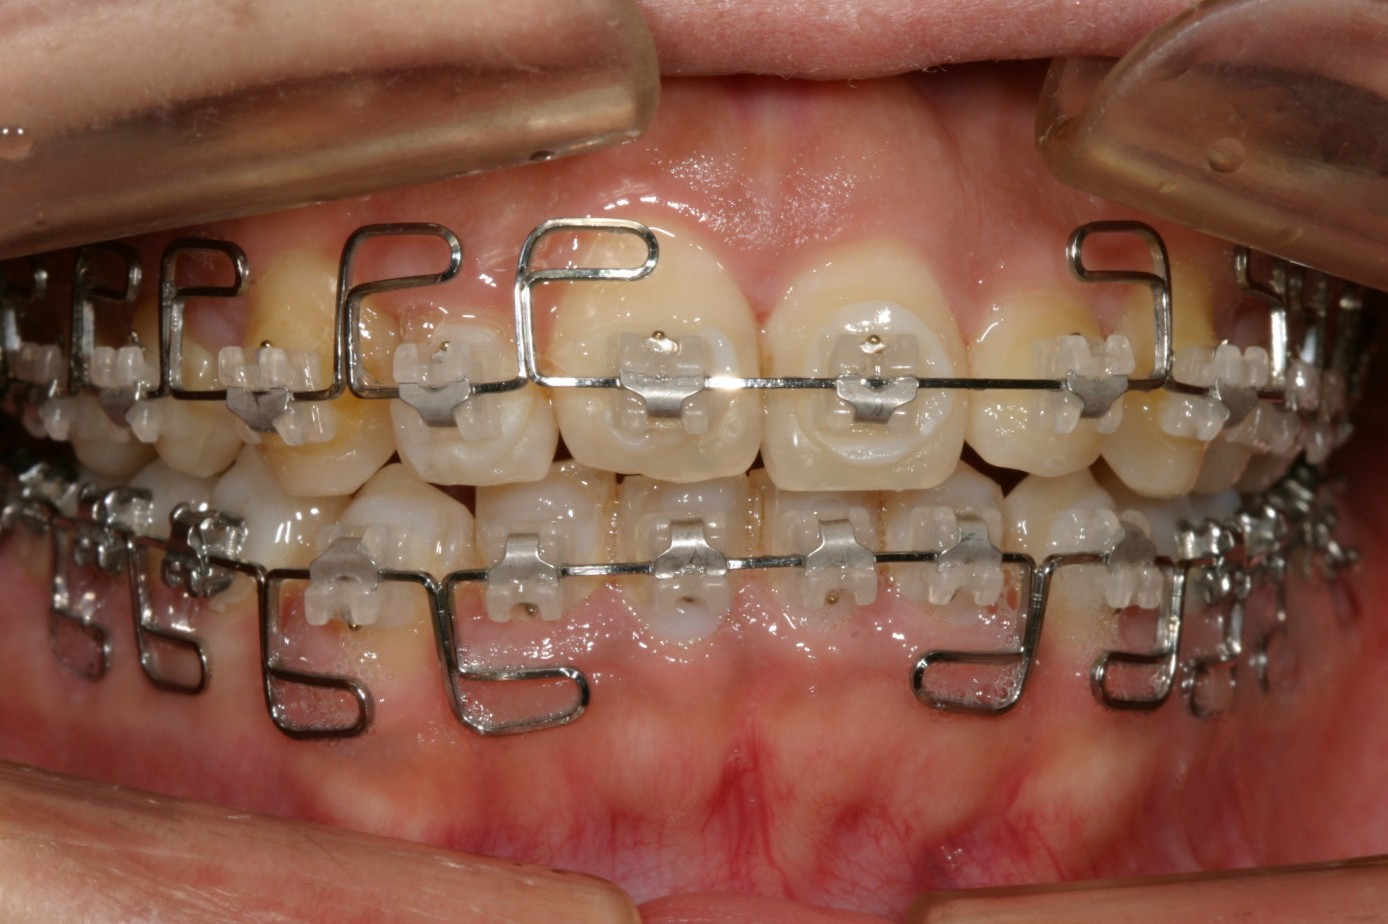

症面観です。 見栄えは悪いですが、ゆっくりとした力がかかるため歯には優しい装置です。

オーバージェットも綺麗に改善しました。

このケースはあまりヘビーなケースでは無いですがこの当時インビザラインがまだこの世になかった時代の患者様でマルチループワイヤーを使用して治療致しました。

今なら典型的なインビザラインケースですね!